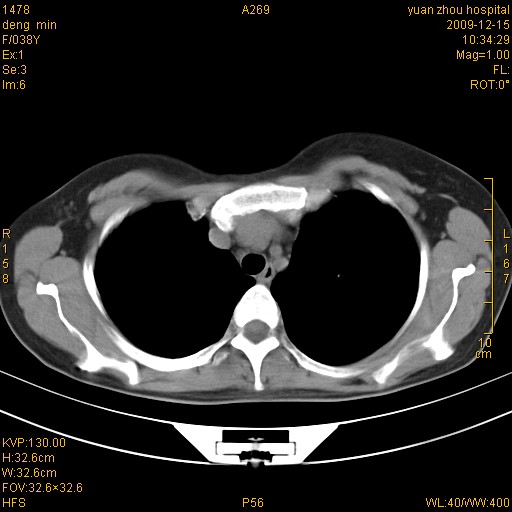

标题: CT23919:F38Y 咳嗽月余 [打印本页]

标题: CT23919:F38Y 咳嗽月余

右肺中下叶、左肺上叶舌段及左肺下叶支气管扩张合并感染。